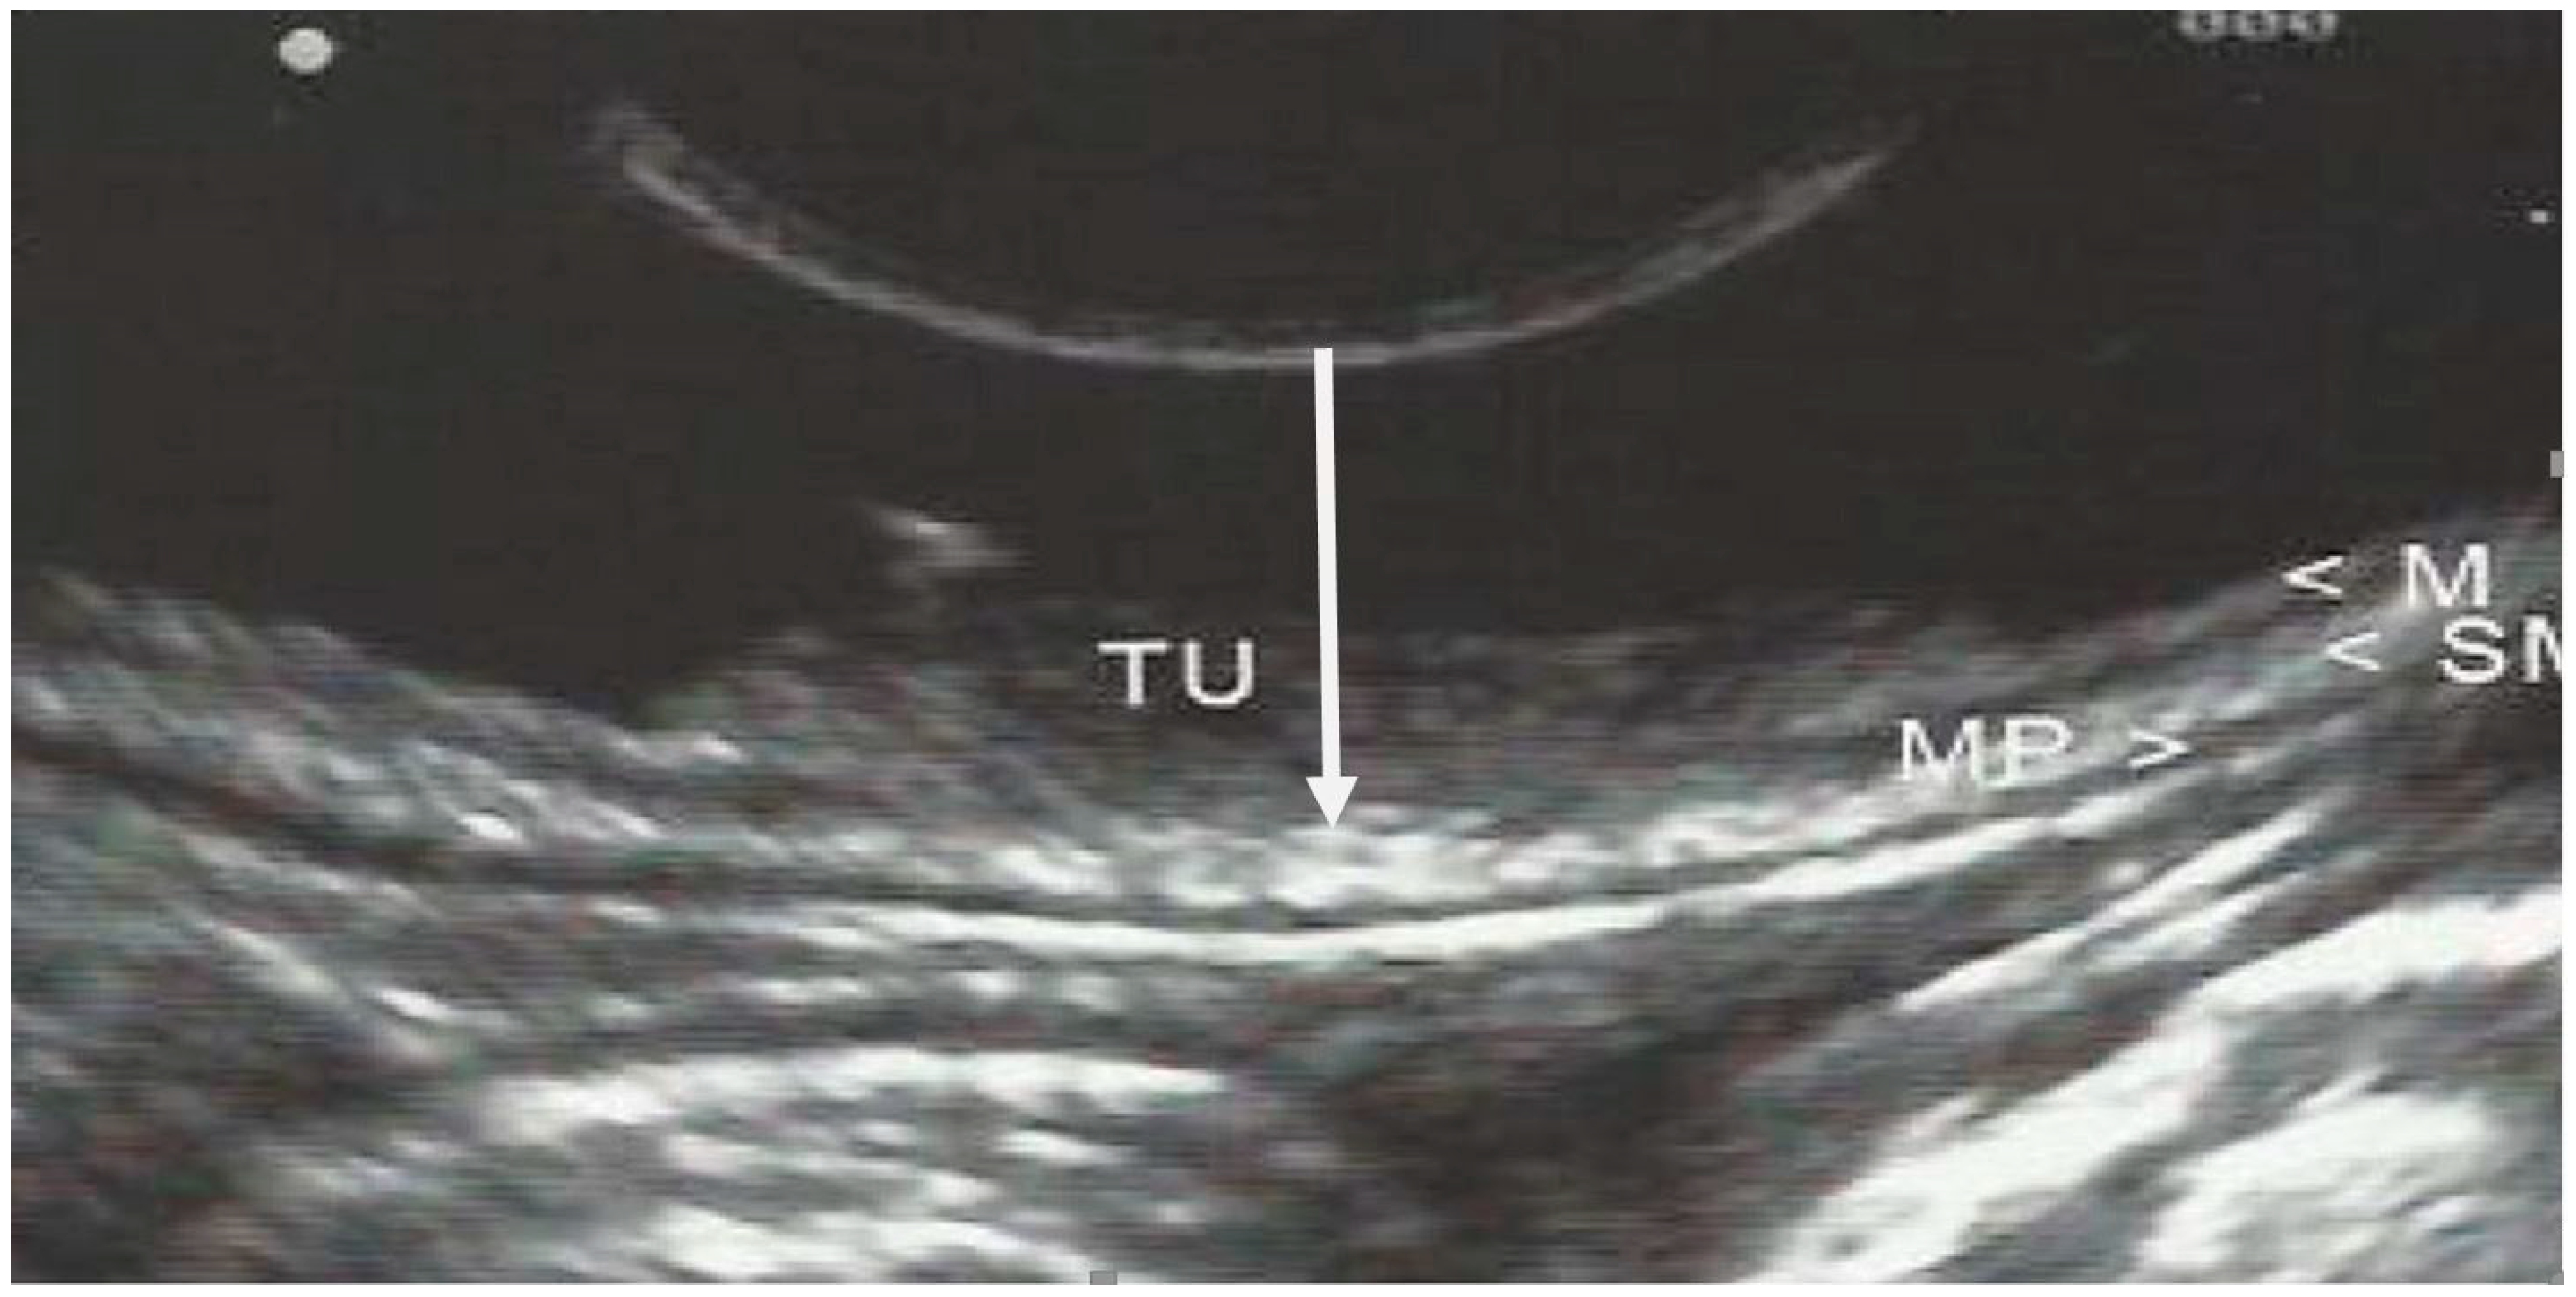

| EUS layer invasion | Mucosa | 155 (52.9) |

| Submucosa | 32 (10.9) | |

| Proper muscle | 32 (10.9) | |

| Subserosa | 74 (25.3) | |

| Histological tumor depth | Mucosa | 136 (46.4) |

| Submucosa | 49 (16.7) | |

| Proper muscle | 34 (11.6) | |

| Subserosa | 64 (21.8) | |